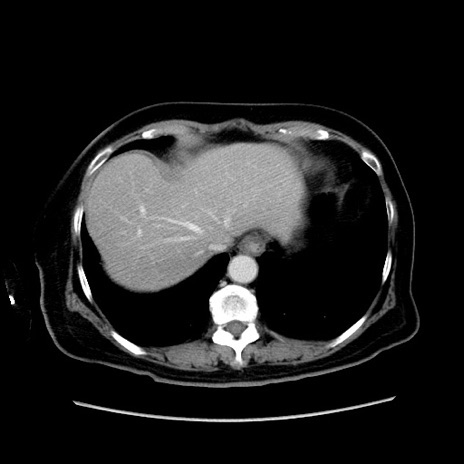

症例19(横断像)

【症例】80歳代女性

【主訴】下腹部痛

【現病歴】約8時間前より下腹部痛の出現あり、救急外来受診。

【既往歴】両側付属器切除

【身体所見】意識清明、下腹部正中に手術痕あり、その部位に一致して圧痛と反跳痛あり。腸蠕動音は亢進。

【データ】WBC 9300、CRP 0.15